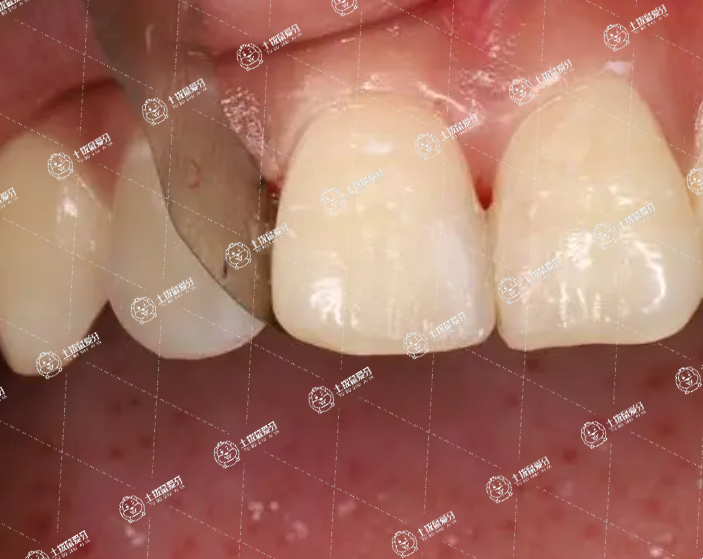

在專業(yè)口腔醫(yī)院可以取下來,通常取下來的全瓷牙會不同程度的遭到破壞,所以不能再次使用。由于全瓷牙制作要求和技術要求都比較高,如果沒有不適或其他原因不需要取下來。除此之外建議患者每半年或一年到醫(yī)院檢查牙齒情況,同時日常生活中要注意口腔衛(wèi)生,飯后及時漱口,可以用含有殺菌成分的漱口水,也盡量不要吃過硬的食物,防止崩裂。

全瓷牙拆下來應該還可以再裝上去,一般需要到口腔科進行粘接修復。全瓷牙屬于修復牙齒的一種方式,但是在取下的時候可能會有一定的難度,而且能起到保護牙齒的作用,因此在拆下來之后會受到損傷,有些已經失去了使用價值,需要重新制作。在使用全瓷牙的時候盡量不要私自拆一下,避免影響到使用后的效果和牙齒健康。做全瓷牙之后要注意口腔的衛(wèi)生,盡量不要長期咀嚼一些堅硬的食物,同時還要選擇正確的方式刷牙。